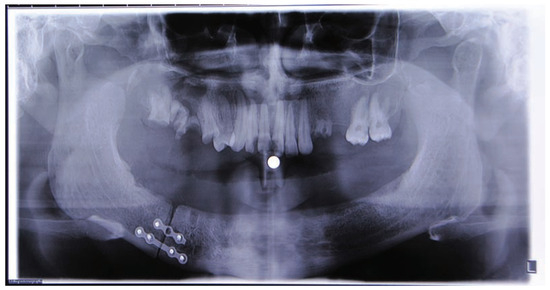

:Case Presentation